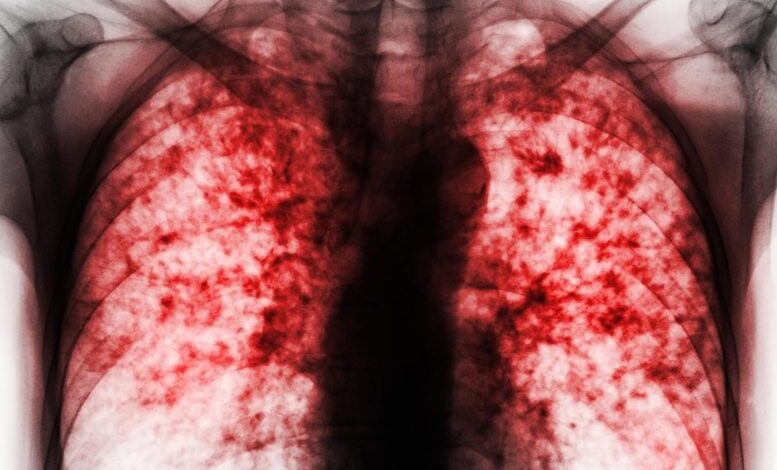

Nejsmrtelnější infekční nemoc na světě naléhavě vyžaduje nová a účinná antibiotika. Vědci vytvořili slibnou novou sloučeninu, která může znamenat velký krok vpřed v celosvětovém úsilí v boji proti tuberkulóze, nejsmrtelnější infekční nemoci v historii lidstva. Podle nové studie zveřejněné v Nature sloučenina nazvaná CMX410 funguje tak, že napadá (…)